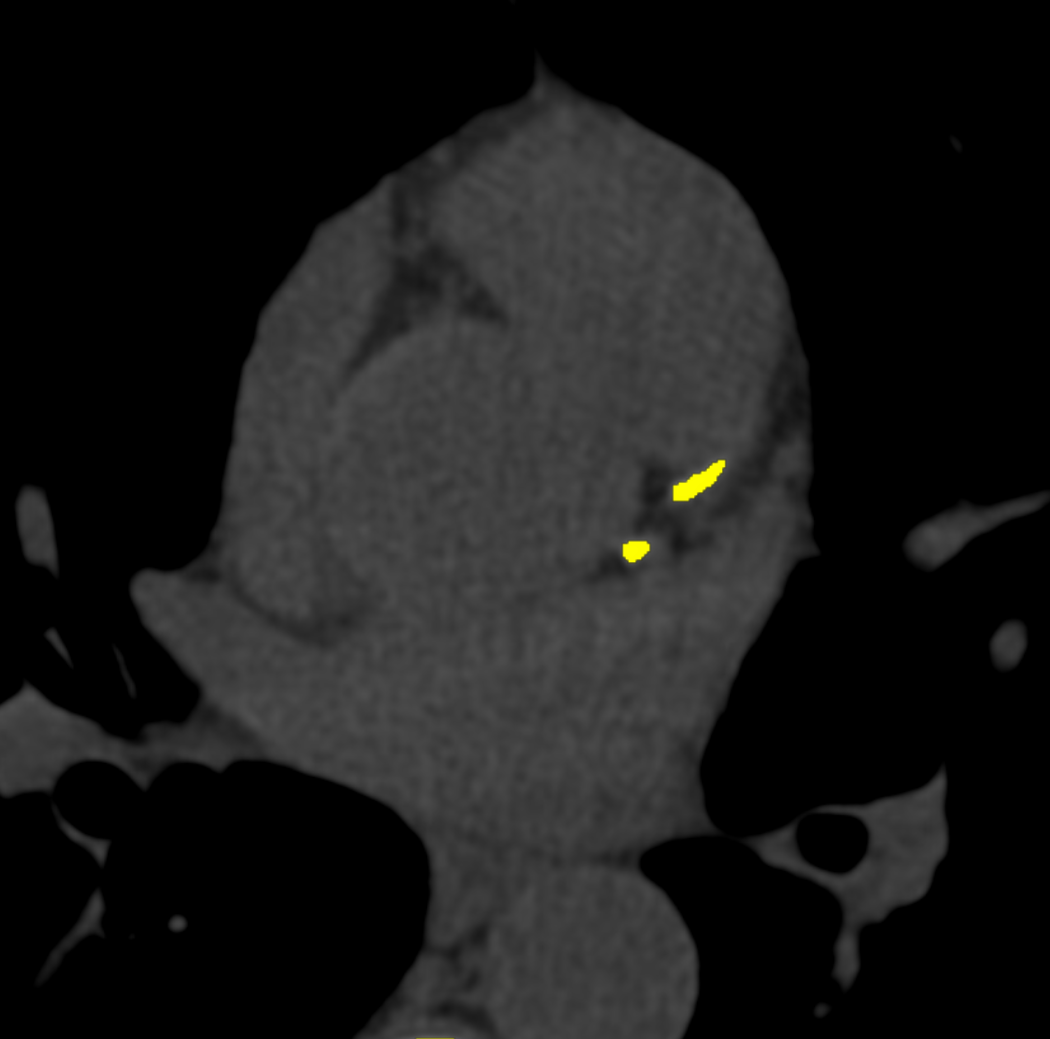

Cardiac CT

CT Coronary Angiogram (CTCA)

CT Coronary Angiography is a non-invasive imaging technique used to visualize the coronary arteries. Using iodinated contrast and advanced CT scanning technology, it helps detect blockages, narrowing, or other abnormalities in the heart’s blood vessels, aiding in the early diagnosis of coronary artery disease (CAD).

Calcium Score

A Calcium Score is a test that uses a CT scan to measure the amount of calcium in the coronary arteries. Calcium buildup is an early sign of atherosclerosis (plaque formation), which can lead to heart disease. The score helps assess the risk of heart attack and determine appropriate preventive measures.